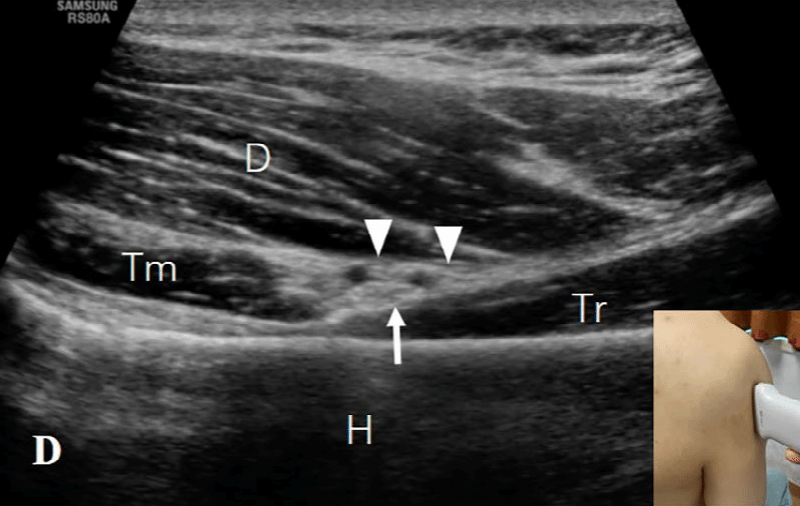

探头的位置根据三个解剖标志来确定:四边孔、肩胛下肌的前方和腋动脉的后方。1)四边孔:由上方的小圆肌、下方的大圆肌、内侧的肱三头肌长头和肱外侧的骨外科颈构成。在评估这个区域时,患者取坐位,肩部处于中立位置。探头沿纵向放置在肩胛骨的外缘和肩胛骨下角下方,以显示冈下肌和小圆肌的短轴切面(图2A)。探头沿着矢状面向外侧移动,直到出现肱三头肌长头腱(图2B)。在这一切面上,小圆肌位于肱三头肌长头的头侧和浅方,大圆肌位于足侧和深方。探头继续向外侧移动,直到出现肱骨干(图2C)。在此切面上,腋神经(AN)和旋肱后动脉位于由头侧的小圆肌(Tm)、足侧的肱三头肌长头(Tr)、浅方的三角肌(D)和深方的肱骨干围成的空间内。通过调整探头,可以更清楚地显示神经血管束(图2D)。

图2D:通过调整探头,可以更清楚地显示腋神经(向上箭)和旋肱后动脉(向下箭头)。